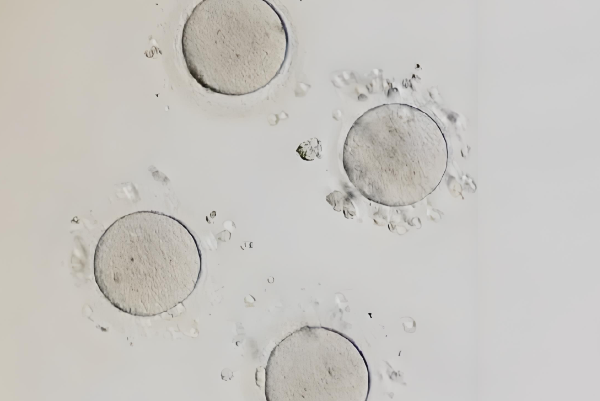

1、卵泡大小均匀且处于静止状态:经过成功的降调后,通过B超可以看到双侧卵巢内的多个小卵泡,它们的大小变得很均匀,直径通常在5毫米以下。更重要的是,这些卵泡都处于“休眠”或“静止”状态,没有哪一个在偷偷地优先发育;